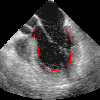

5d reconstruction of the lv myocard from transesophageal echocardiograms

echocardiogram 1 myocard reconstruction 2